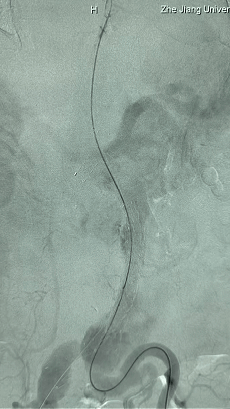

2. 左侧肱动脉入路,超选至降主动脉,更换8F-900mm长鞘,造影提示IV型胸腹主动脉瘤,累及双肾动脉。

3. 经右股动脉导入超硬导丝,然后导入J9集团国际G-Branch 胸腹主动脉主体覆膜支架TAAA3418120e7i1010 一枚,释放主体支架至内分支打开,然后经左侧肱动脉入路,抓捕预置导丝成功后,将长鞘进入内分支出口处。

G-Branch在本例手术中展现出对扭曲解剖结构的出色适应性,针对该患者严重扭曲的瘤颈,支架系统的优异柔顺性使其能够顺利通过复杂路径,完成内脏分支血管的重建。